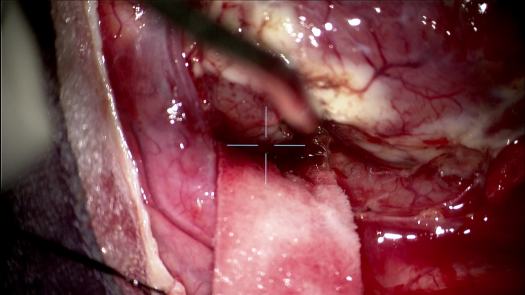

Resezione microchirurgica di tumore cerebrale (glioma alto grado cortico-sottocorticale) frontale dx